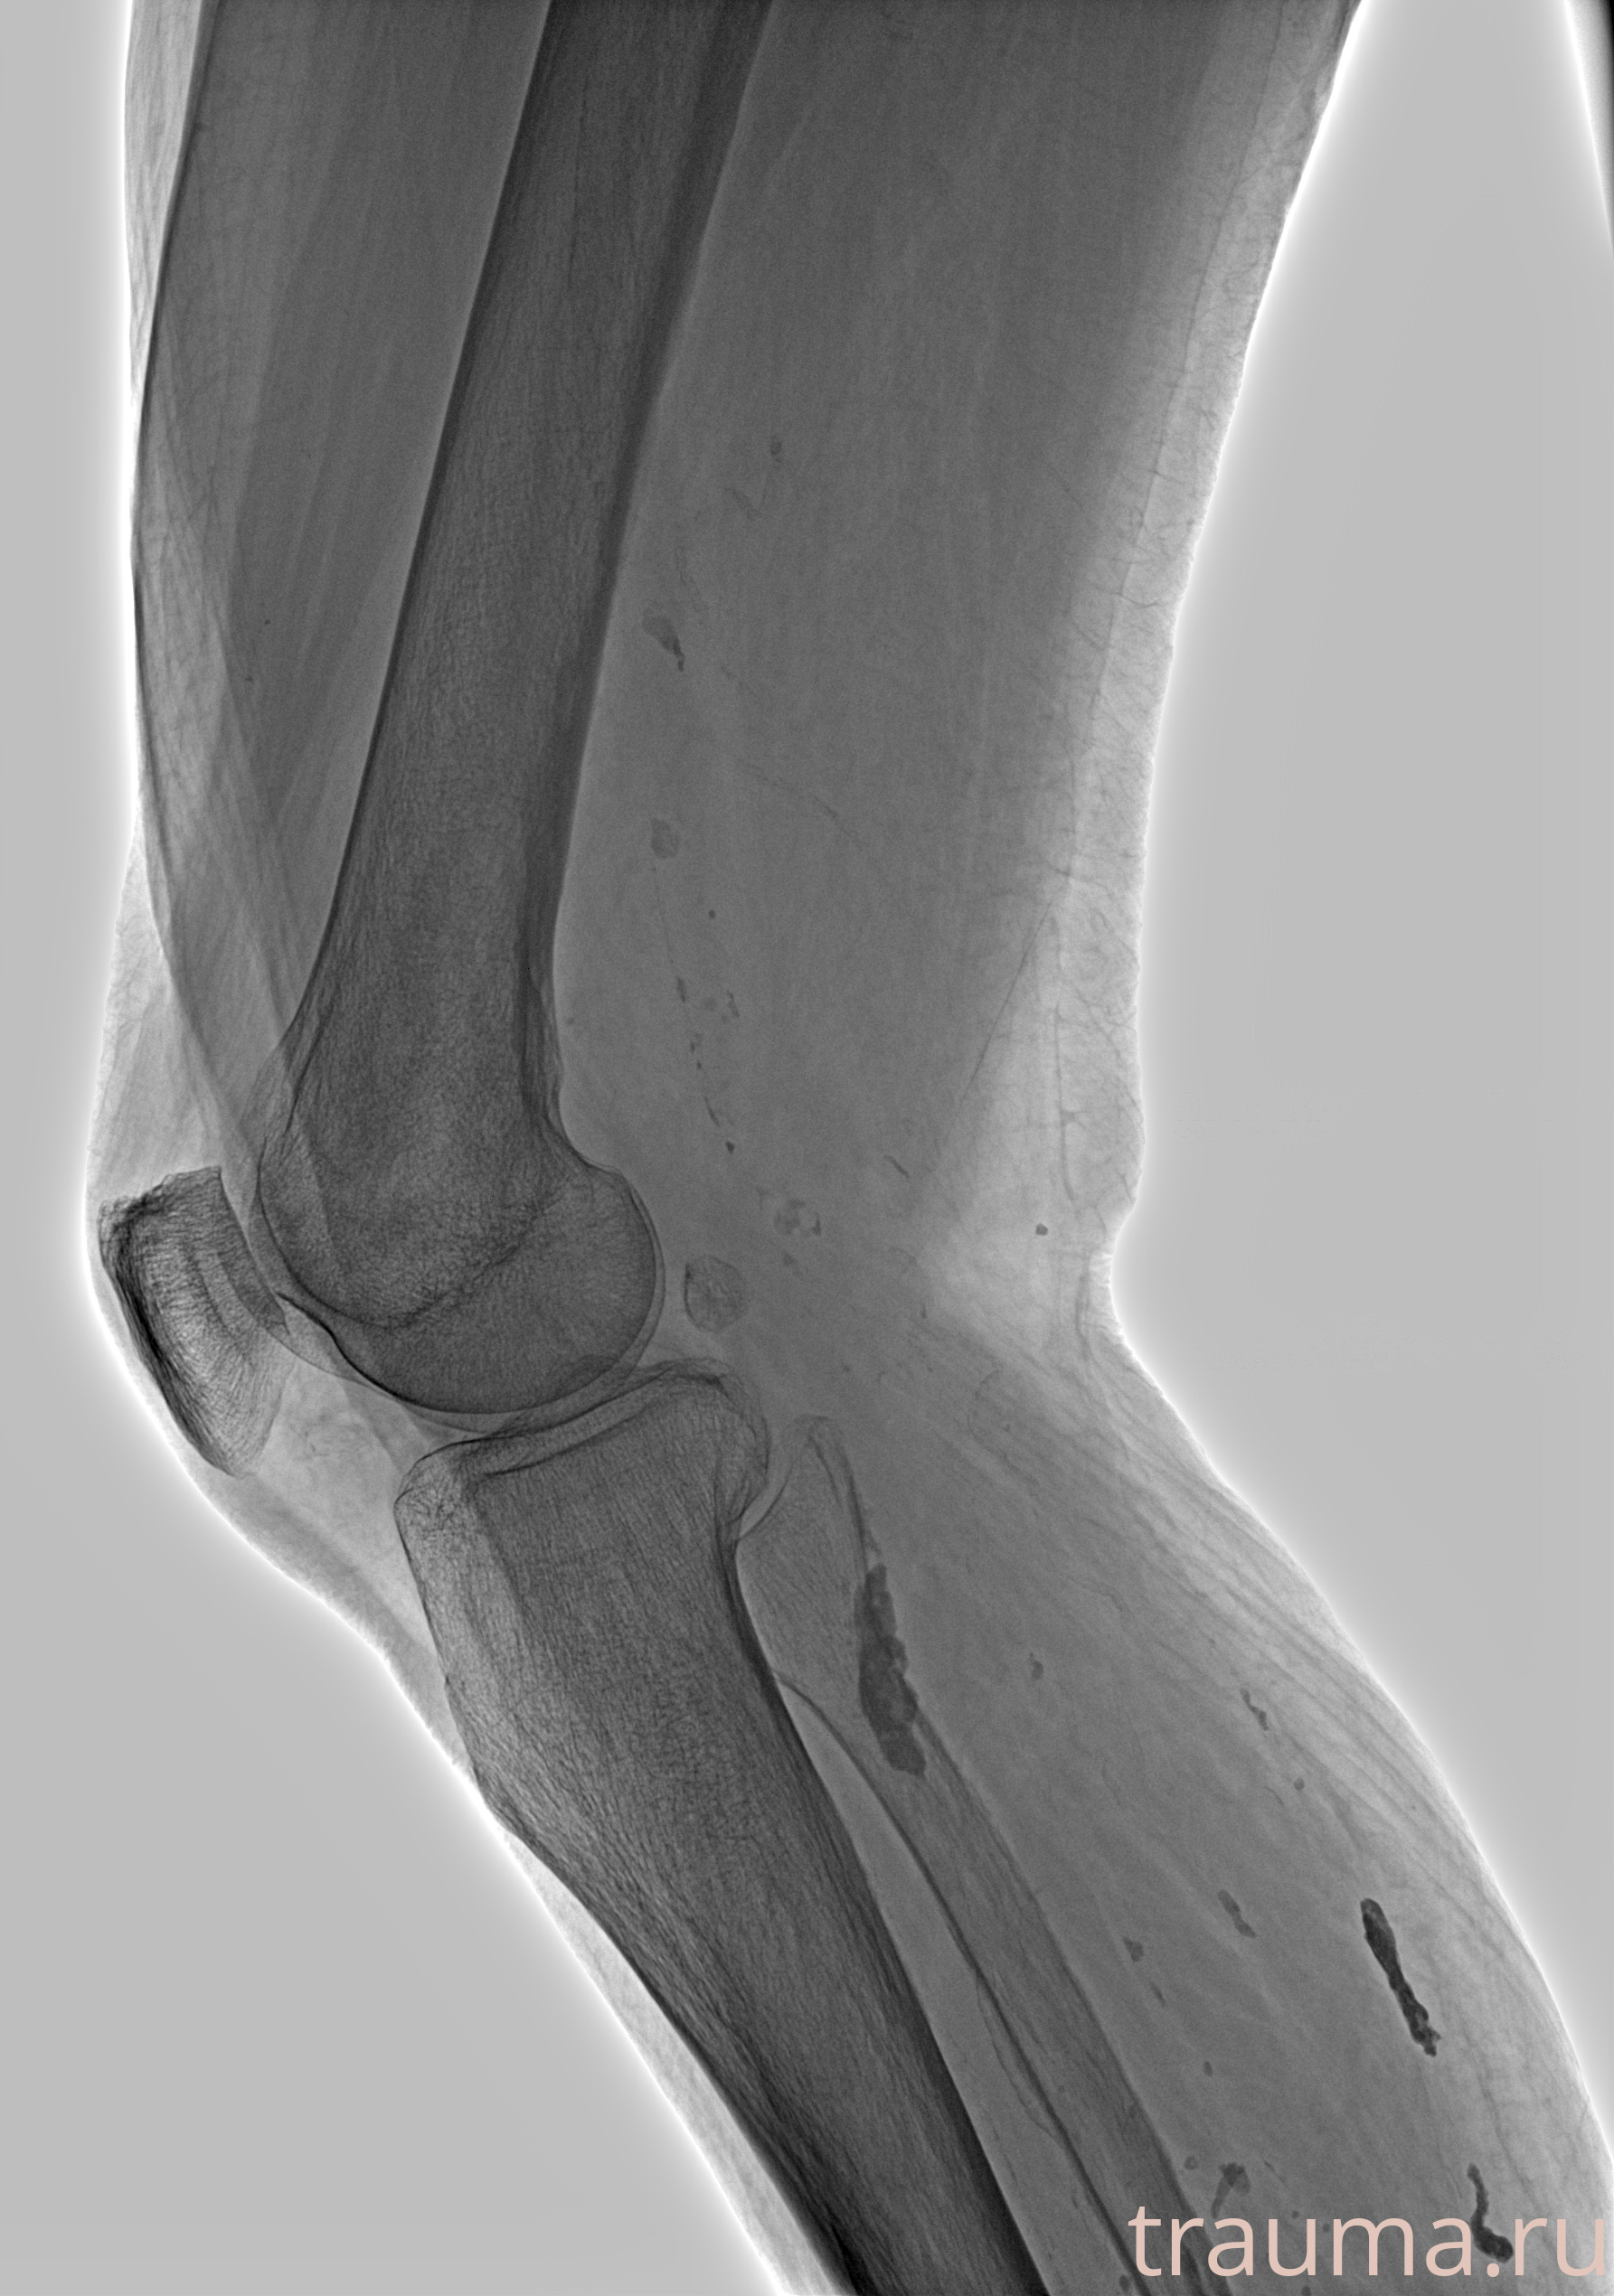

Рентген на дому: по вашему адресу приезжает врач-рентгенолог, травматолог-ортопед с мобильным рентгеновским аппаратом, проводит диагностику травмы или заболевания, делает необходимые рентгенограммы, дает рекомендации по дальнейшему лечению. Получить качественные снимки в домашних условиях возможно благодаря уникальной методике, разработанной МосРентген Центром для института  Склифосовского